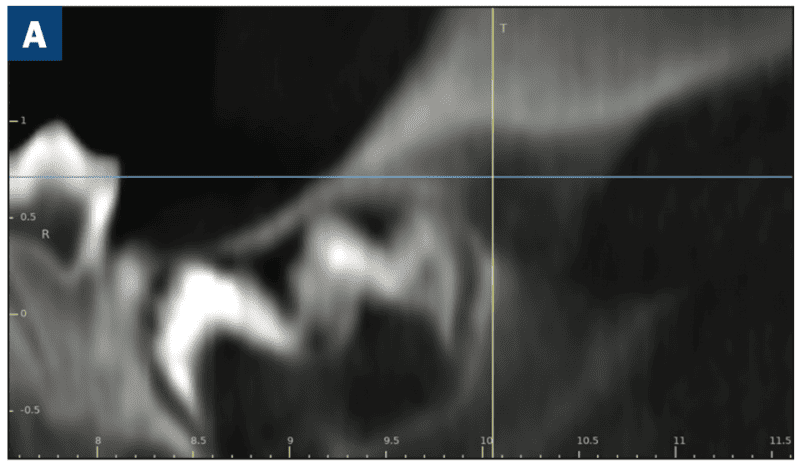

As reported in the April 2023 issue of Journal of Oral and Maxillofacial Surgery, complete molar agenesis was achieved in 100% of TriAgenics’ 3TBA procedures using micro-ablation treatment cycles of 60 seconds or less. Radiographic and histological assessment indicated no presence of treated tooth bud tissue 28 days following 3TBA treatment. Figure 1a shows a typical one-day, pre-operative image of a targeted tooth bud. Figure 1b shows 28-day, post-operative healing results. Histological evaluation at 28-days post 3TBA treatment confirms the presence of complete bony infill with trabecular new bone growth and no detectable viable tooth bud tissue.

Figure 1a. Targeted porcine tooth bud (crosshairs) one day pre-operative.